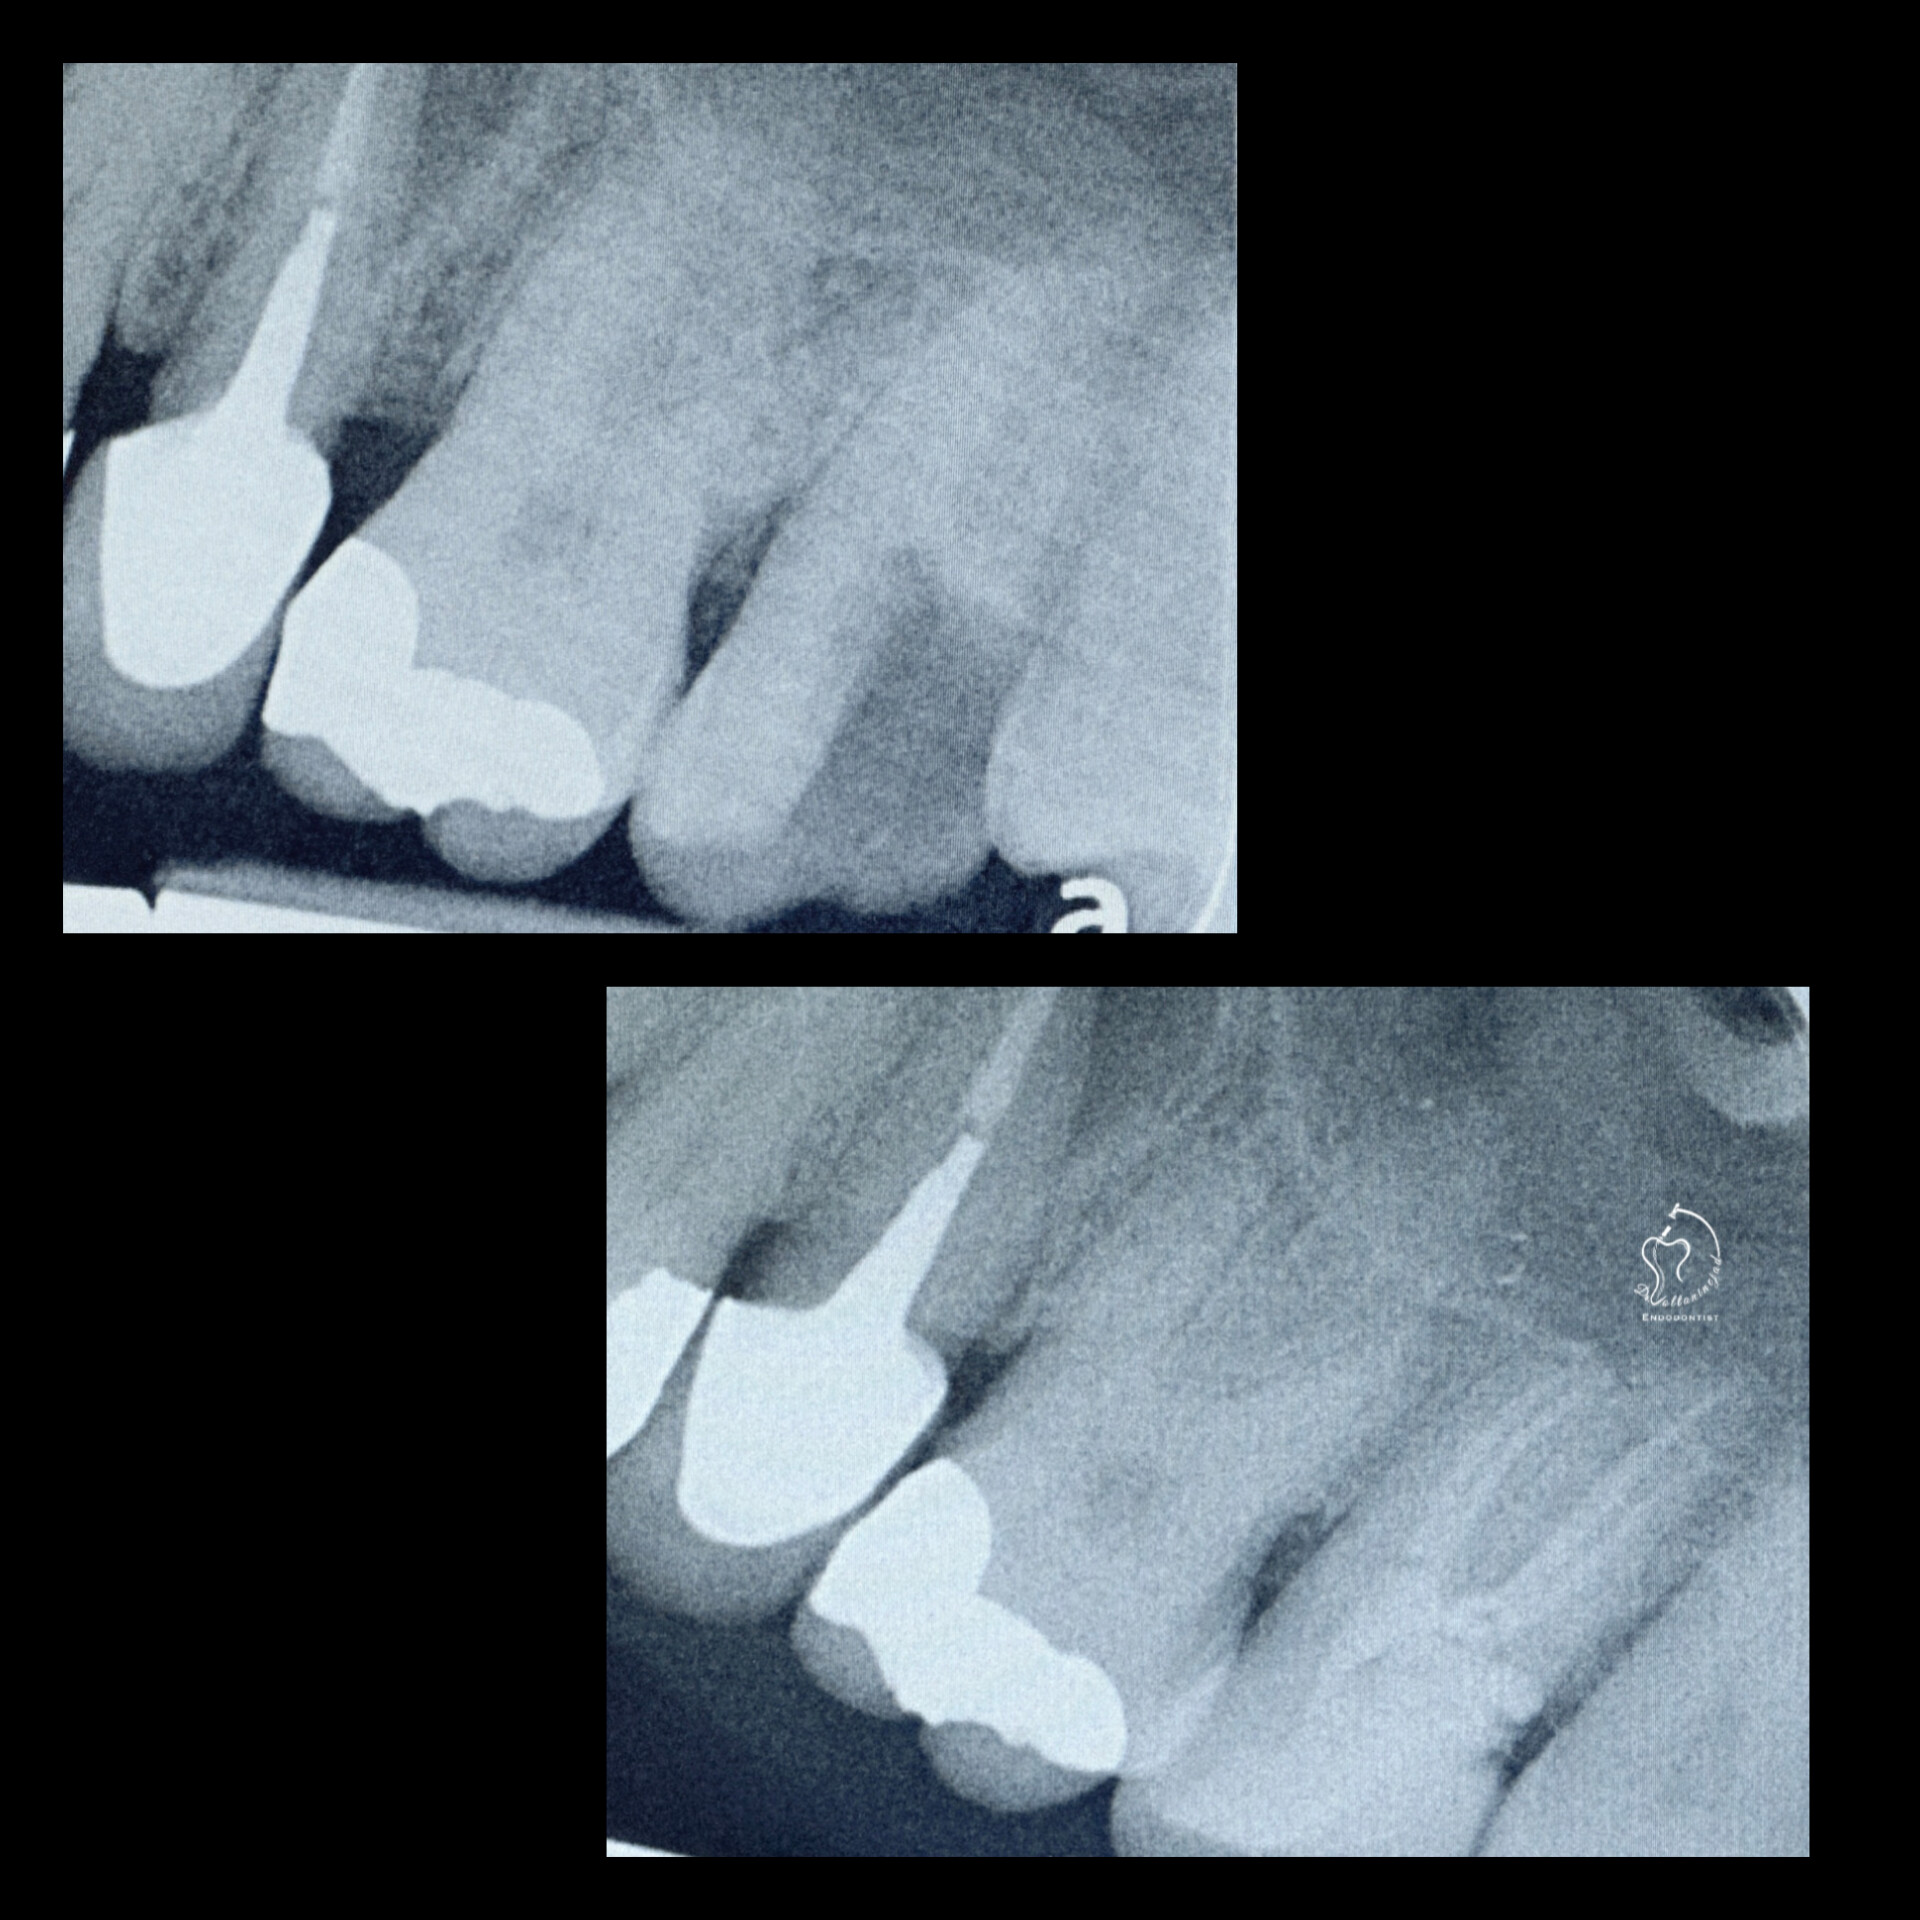

🔹 درمان ریشه مجدد (Retreatment) در دندان پرمولر

• شرح کوتاه: درمان قبلی نامناسب و همراه با عفونت بود. درمان مجدد با میکروسکوپ انجام شد.

• نتیجه: ترمیم ضایعه استخوانی و بازگرداندن دندان به شرایط سالم.